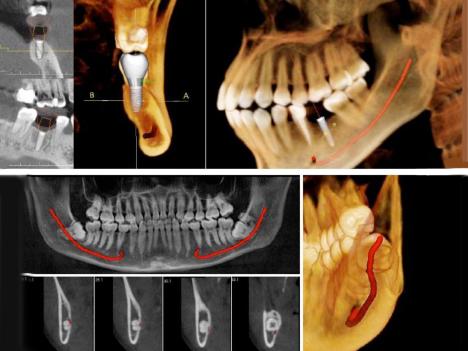

斷層掃瞄 / 解析骨質、神經血管,模擬植牙位置